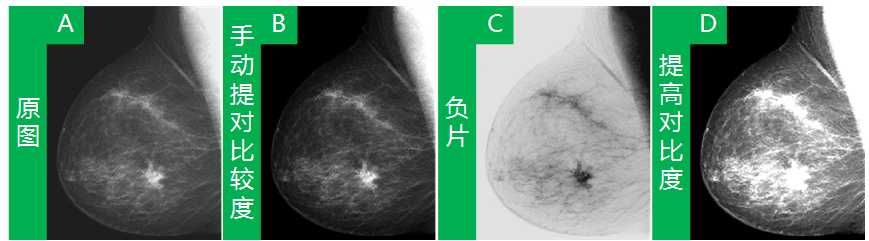

Low_High=strechlim(f),就是帮我们找到图像f中的像素幅值的最大值和最小值,如果f是一个单值图像,那么Low_High就是一个行向量(1*2的矩阵),如果f是一个彩色图像,那么Low_High就是一个3*2的矩阵。当我们找到f图像的最小,最大像素幅值后,再将其映射到整个像素区间[0 1],也就是书中所讲,实现对比度拉伸,可以得到不错的效果。如下图,从A图到D图,D图就是使用了strechlim(f),然后使用D=imadjust(f,Low_High,[0 1]);得到的图像,很是清晰。